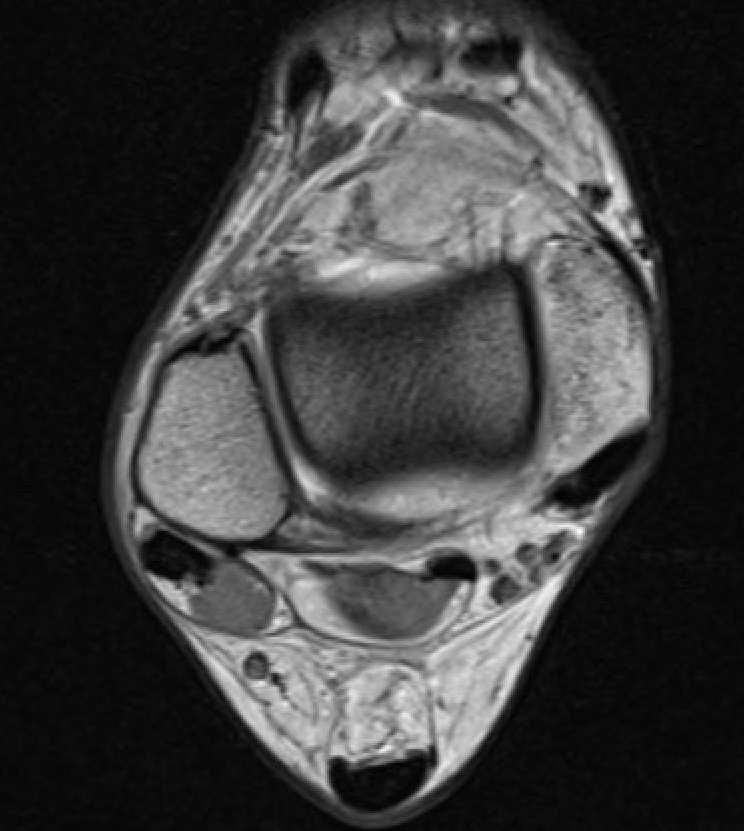

PTFL